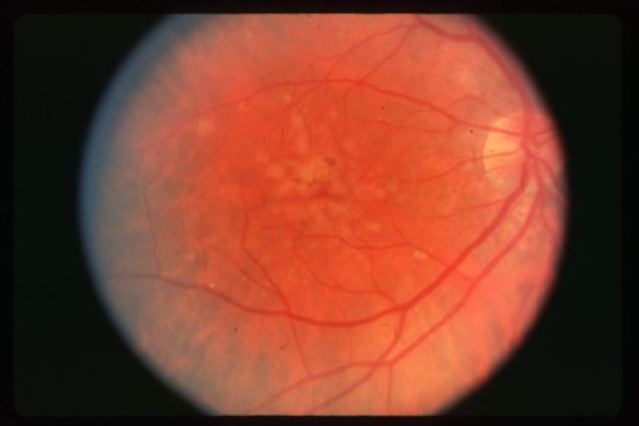

drusen

drusen

hard drusen

soft drusen

soft drusen

soft drusen

soft drusen